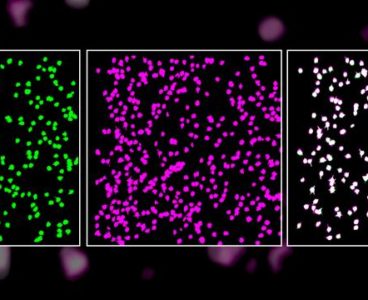

Neurons Reliably Respond to Straight Lines

Single neurons in the brain’s primary visual cortex can reliably detect straight lines, even though the cellular makeup of the neurons is constantly changing, according to a new study by Carnegie Mellon University neuroscientists, led by Associate Professor of Biological Sciences Sandra Kuhlman. The study’s findings, published in Scientific Reports on Oct. 16, lay the…